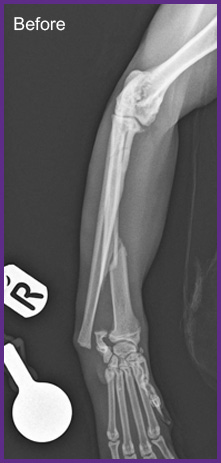

我們提供留院服務並擁有相應的治療設施,亦是小數備有CT電腦掃描及MRI磁力共振等大型醫療儀器的診所及醫院。